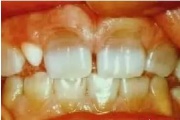

Vali sind huvitav pilt ja me näitame sellega seotud haigust ja sümptomeid